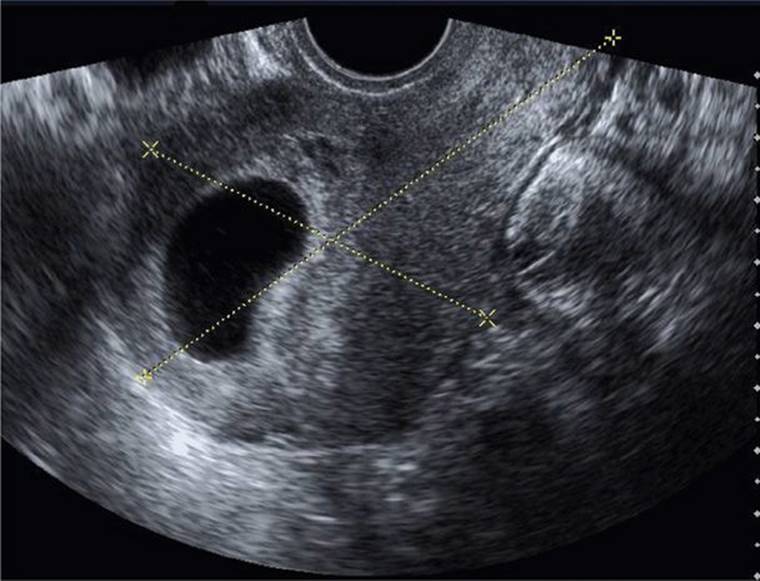

This historical description of missed abortion is in contrast to that defined currently based on results of serial serum β-hCG assays and transvaginal sonography (Fig. 18-4). With rapid confirmation of fetal or embryonic death, many women choose uterine evacuation. Although many classify these as a missed abortion, the term is used interchangeably with early pregnancy loss or wastage (Silver, 2011).

FIGURE 18-4 Transvaginal sonogram displays a large anechoic sac consistent with an anembryonic gestation. Calipers measure uterine length and anteroposterior thickness in a sagittal plane.